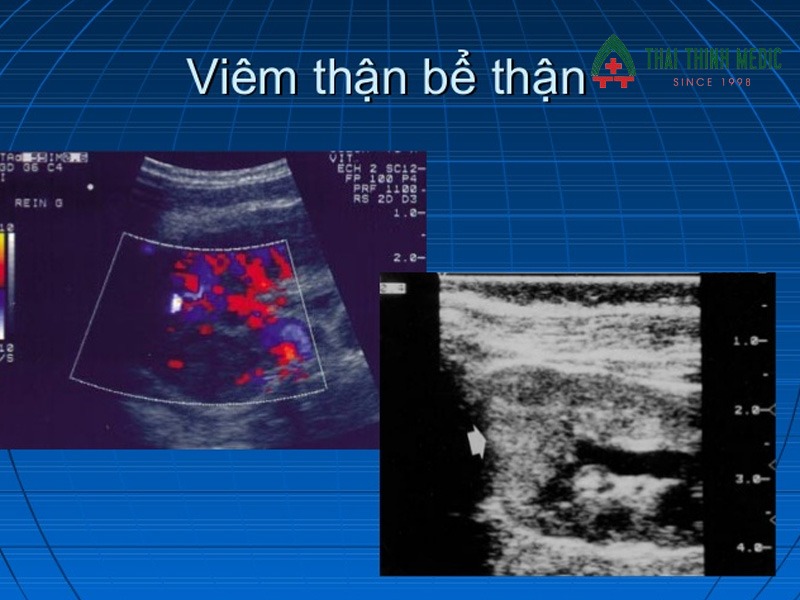

Viêm thận, bể thận

Viêm thận, bể thận là một trong những biến chứng phổ biến và nguy hiểm nhất khi viêm đường tiết niệu không được kiểm soát. Tình trạng này xảy ra khi vi khuẩn từ bàng quang lan ngược lên thận, gây viêm nhiễm tại nhu mô thận và hệ thống bể thận. Nếu không điều trị kịp thời, viêm thận có thể làm tổn thương cấu trúc thận, ảnh hưởng đến chức năng lọc máu và thải độc của cơ thể.

Người bệnh thường có biểu hiện rõ rệt như sốt cao, đau vùng lưng hoặc hông, kèm theo các triệu chứng tiểu buốt, tiểu rắt. Trong trường hợp nặng, tình trạng viêm kéo dài có thể dẫn đến sẹo thận hoặc suy giảm chức năng thận vĩnh viễn.

Viêm thận, viêm bể thận